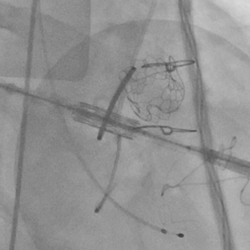

黄焕雷主任带领具有丰富经验的心脏麻醉医师、体外循环师、超声心动图医师、手术室、心外重症监护室、心脏导管室多学科团队,联合心内科专家谢年谨主任,为蔡先生实施小切口下、介入途径的主动脉瓣“瓣中瓣”、二尖瓣“环中瓣”的同期植入手术:黄主任首先在患者左前胸做一小切口,暴露患者的心尖,在跳动的心脏上“绣”上荷包作为介入导管、瓣膜的植入“门户”;随后,黄焕雷主任在超声心动图、放射透视的引导下,将一钢针在患者心尖“扎”入患者心脏内,为之后的瓣膜植入作为引导,具体来说就是将预先选择适合患者大小的生物瓣膜折叠、压缩入细长的输送管道内,好比将瓣膜这一“弹头”安放在输送导管这颗精准制导的“火箭”上,而黄主任的双手则控制这一精准发射和制导,再将瓣膜输送到主动脉合适的位置后释放,新的主动脉瓣便牢固地“卡”在了原有的主动脉瓣架内。经过透视和超声心动图评估,主动脉瓣位置合适,开放、闭合功能良好。随后,黄主任通过这一根钢针和输送导管,利用类似的方式,调整“火箭”的发射轨道,在原有二尖瓣人工瓣环内植入预先选择好大小的二尖瓣生物瓣膜,经过影像学方式评估,新植入的二尖瓣生物瓣工作良好。

球扩释放二尖瓣环中瓣